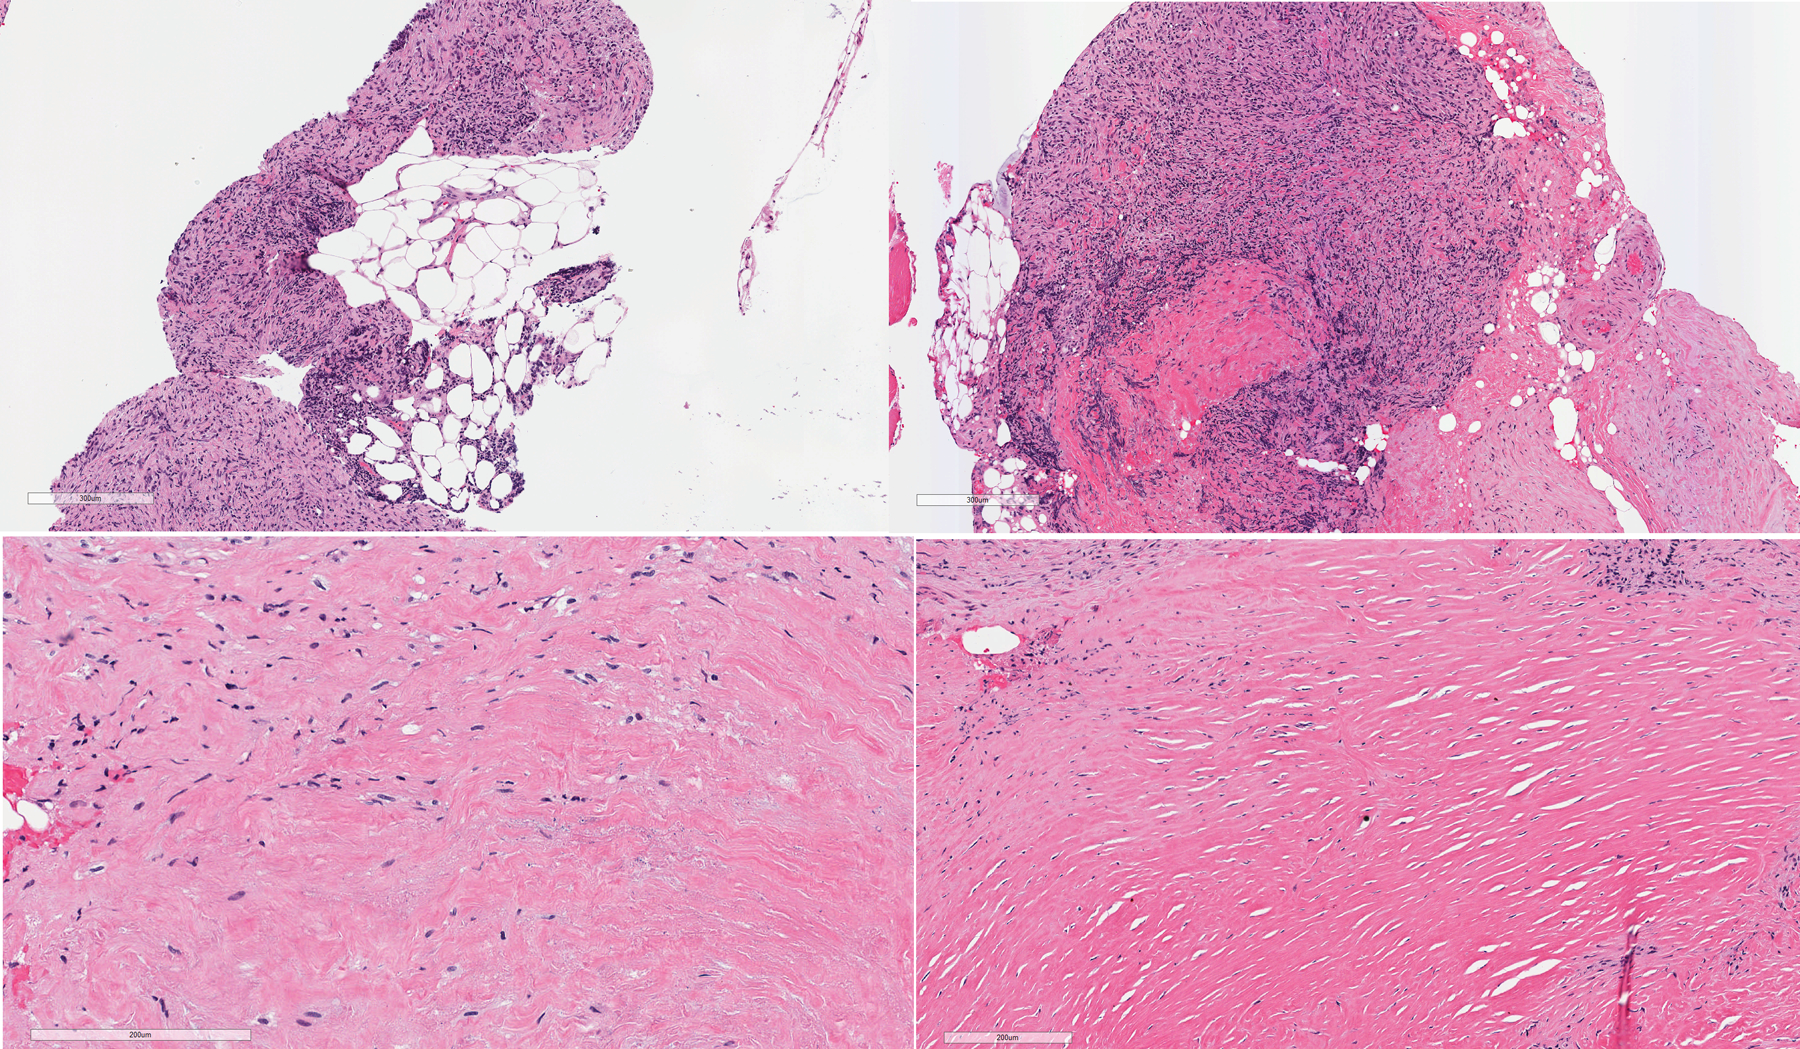

Sarcomatoid mesotheliomas can be challenging to diagnose on small biopsy specimens, where limited material may preclude definitive assessment of invasion and lesional cells can have relatively bland cytology with no mesothelial marker expression. We report a case of a patient who presented with a pleural effusion and had subsequent pleural biopsy that showed a bland, uniform spindle cell proliferation in a mildly myxoid background. There was little if any collagen; no chest wall, soft tissue, or fat; and mesothelial markers were negative. The cells were positive for pancytokeratin and GATA3 by immunohistochemistry, and in situ hybridization showed a "negative" result for homozygous loss of CDKN2A; however, there was partial (heterozygous) loss of one allele. A diagnosis of atypical spindle cell proliferation was made based on these findings. Several months later, the patient had a repeat pleural biopsy that showed spindled cells with more pleomorphism, areas of invasion into the chest wall, and the same partial loss of CDKN2A, consistent with a sarcomatoid mesothelioma. This case underscores the challenges present on small biopsy specimens, the fact that sarcomatoid mesotheliomas can be relatively bland appearing with focal pleomorphism, and that heterozygous loss of CDKN2A should be considered a positive result indicative of a neoplastic process.